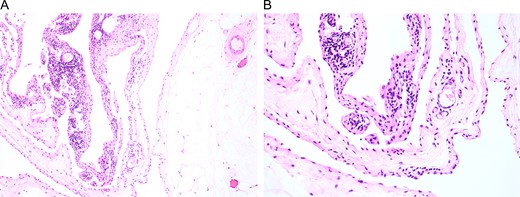

Surgical specimens were collected and stained with H&E. Representative images are shown at (A) low and (B) high magnification, which affirmed the diagnosis of cystic lymphangioma.

The patient was brought back to the outpatient breast center to discuss imaging results and surgical options. She elected to proceed with surgical excision of the mass given the size and its distorting nature (Fig. 2A). Due to insurance issues, the patient was unable to have immediate reconstruction with a plastic surgeon. One week later, the patient was scheduled for excision of the left breast mass (Fig. 2B and C). She tolerated the procedure well without any complications, and she was comfortable going home the same day on minimal analgesia. The final pathology report was consistent with lymphangioma (Fig. 3), showing a 21.0 × 20.0 × 6.0 cm3 mass that contained nearly 800 mL of serosanguinous fluid. The cyst wall varied in thickness from 0.1 to 0.2 cm. Post-operatively, the patient did well with no wound complications or complaints. She was referred to plastic surgery for delayed reconstruction at an outside institution.